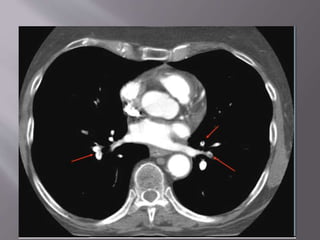

• Direct visualization of emboli.

• Both parenchymal and mediastinal structures

can be evaluated.

•Optimally used when incorporated into a

validated diagnostic decision tree

• Direct visualizationof emboli. • Both parenchymal and mediastinal structures can be evaluated. •Optimally used when incorporated into a validated diagnostic decision tree